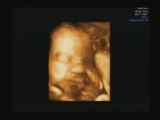

echographie 3d

2009-02-03

ECHOGRAPHIE 3D 24 semaines